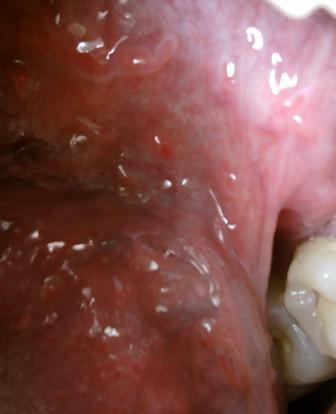

石家庄九州皮肤病医院 > 尖锐湿疣 > > > 预防尖锐湿疣应该从自身做起尖锐湿疣病毒是很顽固的,因此患病之后应该及早诊治,毕竟初期是治疗疾病的最佳时期,为了身体健康,也应该注意做好疾病的预防工作,预防尖锐湿疣就应该从尖锐湿疣的发病原因着手。

预防尖锐湿疣应该从自身做起尖锐湿疣之所以发病,一般是通过以下几种途径传染病毒而发病的,直接接触传染,间接接触传染和母婴传染等等。预防尖锐湿疣最为重要的就是要杜绝乱性。选择适合自己的治疗方案是很关键的。盲目治疗,只会导致疾病是越来越严重。病之后一定要及时去医院积极配合医生进行治疗,争取可以做到早发现早治疗。